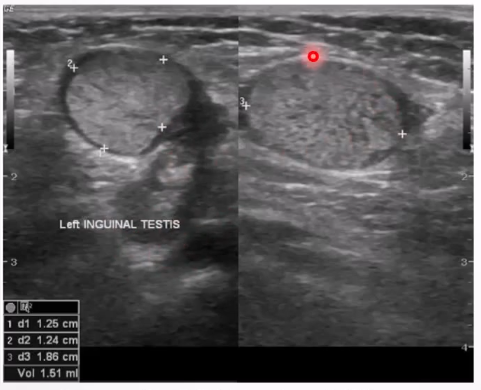

Scrotal Pearl: Benign macrocalcifications in scrotum, occur due to microtrauma.

Clinical Presentation: Usually asymptomatic; diagnosed incidentally.

Ultrasound Appearance:

Small mobile hyperechoic extratesticular focus within the tunica space; pearl may show posterior acoustic shadowing if large; can appear as free floating if there is a hydrocele